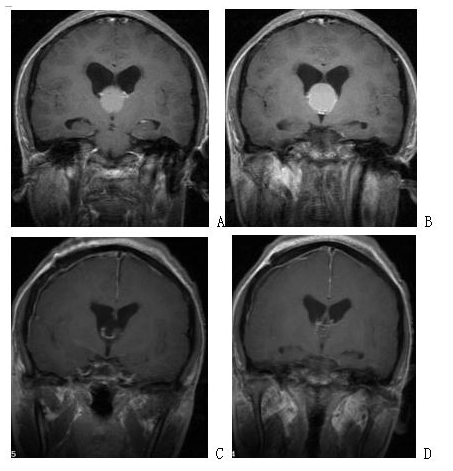

Neurosurgical Oncology Ward 3Neurosurgical Oncology Ward 3 (Middle-line skull base tumors and neuroendoscopy) Specialized features The Neurosurgical Oncology Ward 3 is characterized by the clinical application of neuroendoscopic technology. The annual number of neuroendoscopic surgeries exceeds 1200, and the quantity and quality of neuroendoscopic surgeries are leading domestically and internatio…